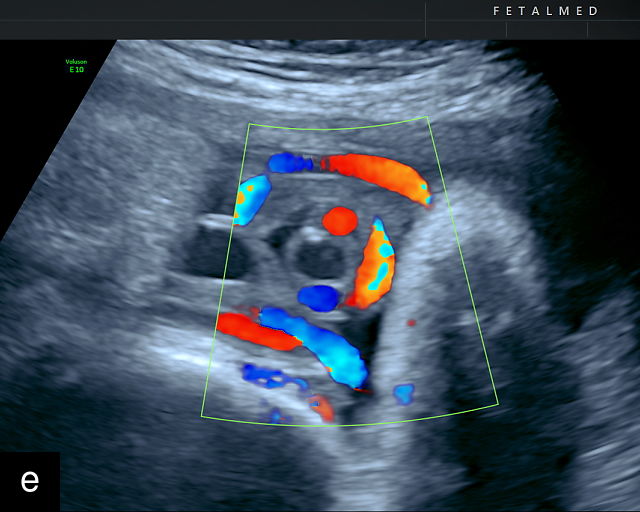

Velamentous cord insertion

When the umbilical cord inserts into the membranes rather than the main placental mass, it is known as a velamentous cord insertion (VCI).191 In this condition, unprotected fetal vessels traverse the membranes for a variable distance before inserting into the placental edge. Velamentous cord insertions are relatively common, occurring in approximately 1% of pregnancies and about 10% of twin pregnancies.191 A large population-based study from Norway reported a 1.5% prevalence of VCI in singleton pregnancies compared to 6.0% in twins.227 Risk factors for VCI include twin gestation, pregnancy conceived via assisted reproductive technology and advanced maternal age.34,236,237,238,239

VCI is associated with an increased risk of fetal structural abnormalities.240 When a VCI is identified, a detailed fetal anatomical survey is recommended. VCI is also linked to adverse perinatal outcomes, including intrauterine fetal demise, FGR, preterm birth and complications during delivery, such as cord avulsion leading to retained placenta and an increased risk of postpartum hemorrhage.241,242,243,244 VCI has also been associated with increased risks for cerebral palsy in the offspring.7 While rare, spontaneous rupture of VCIs has been reported, potentially resulting in stillbirth or other adverse outcomes. In the absence of vasa previa, however, labor and vaginal delivery are typically recommended. Serial ultrasound examinations to assess fetal growth are advised when VCI is detected during prenatal ultrasound. Importantly, VCI in monochorionic twins is associated with an increased risk for TTTS, selective FGR and birth-weight discordance.245,246,247

Ultrasound is the primary diagnostic method for identifying VCI. Normally, the cord inserts into the center or edge of the placenta and is fully protected by Wharton’s jelly. In contrast, a velamentous cord insertion is visualized on ultrasound as the cord inserting into the membranes, with unprotected fetal vessels running to the placental margin (Figure 20; Video 11). Color flow Doppler and three-dimensional ultrasound can enhance diagnostic accuracy. Velamentous cord insertion may also occur into the dividing membrane in a multifetal pregnancy (Figure 20e). When unprotected fetal vessels from a VCI cross over the cervix, the condition is termed vasa previa, posing a significant risk of fetal exsanguination if these vessels rupture. Because VCI is a strong risk factor for vasa previa, a color flow Doppler sweep over the cervix is recommended when VCI is identified. If concerns about vasa previa persist, transvaginal ultrasound with color Doppler may be performed for confirmation.30

20

Nomiyama and colleagues conducted a study in which color Doppler screening of placental cord insertion was routinely performed on 587 patients during second-trimester anatomy scans.248 They successfully identified the placental cord insertion in 586 cases (99.8%) and correctly diagnosed five cases of VCI, with one false-positive result.248 The study reported a sensitivity of 100%, specificity of 99.8%, positive predictive value of 83% and negative predictive value of 100%. However, the study population in Japan had a significantly lower average body mass index (BMI) compared to populations in the Western world. Increased BMI, fetal position, uterine fibroids and posterior placenta may hinder visualization of the cord, making these results less generalizable to populations with higher BMI prevalence.

Sepulveda and colleagues evaluated 832 patients during the second and third trimesters using color Doppler and successfully visualized placental cord insertion in 825 cases (99%), diagnosing seven cases of VCI.249 These authors, in a separate study, also screened 533 pregnancies during the first trimester and correctly identified five cases of VCI.250

In the USA, consensus guidelines recommend assessing placental cord insertion during the second-trimester anatomical ultrasound examination when feasible. This approach is being increasingly recommended in other countries.251 At our center, this assessment has been routinely performed as part of the second-trimester anatomy scan for several years, and we strongly advocate for its inclusion as a standard component of the examination.